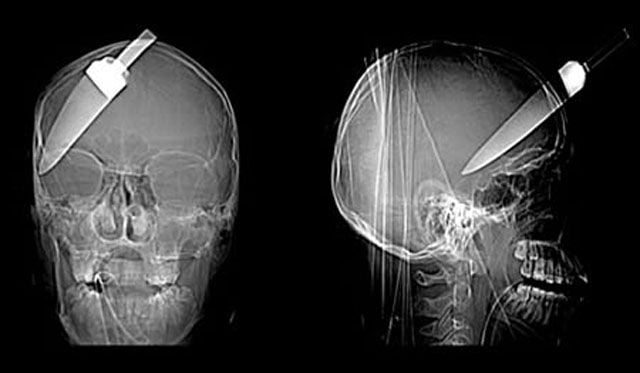

A 16-year-old cheated death when a 5-inch knife was plunged into his head. The teenager was rushed to hospital with the kitchen knife still stuck in his forehead.